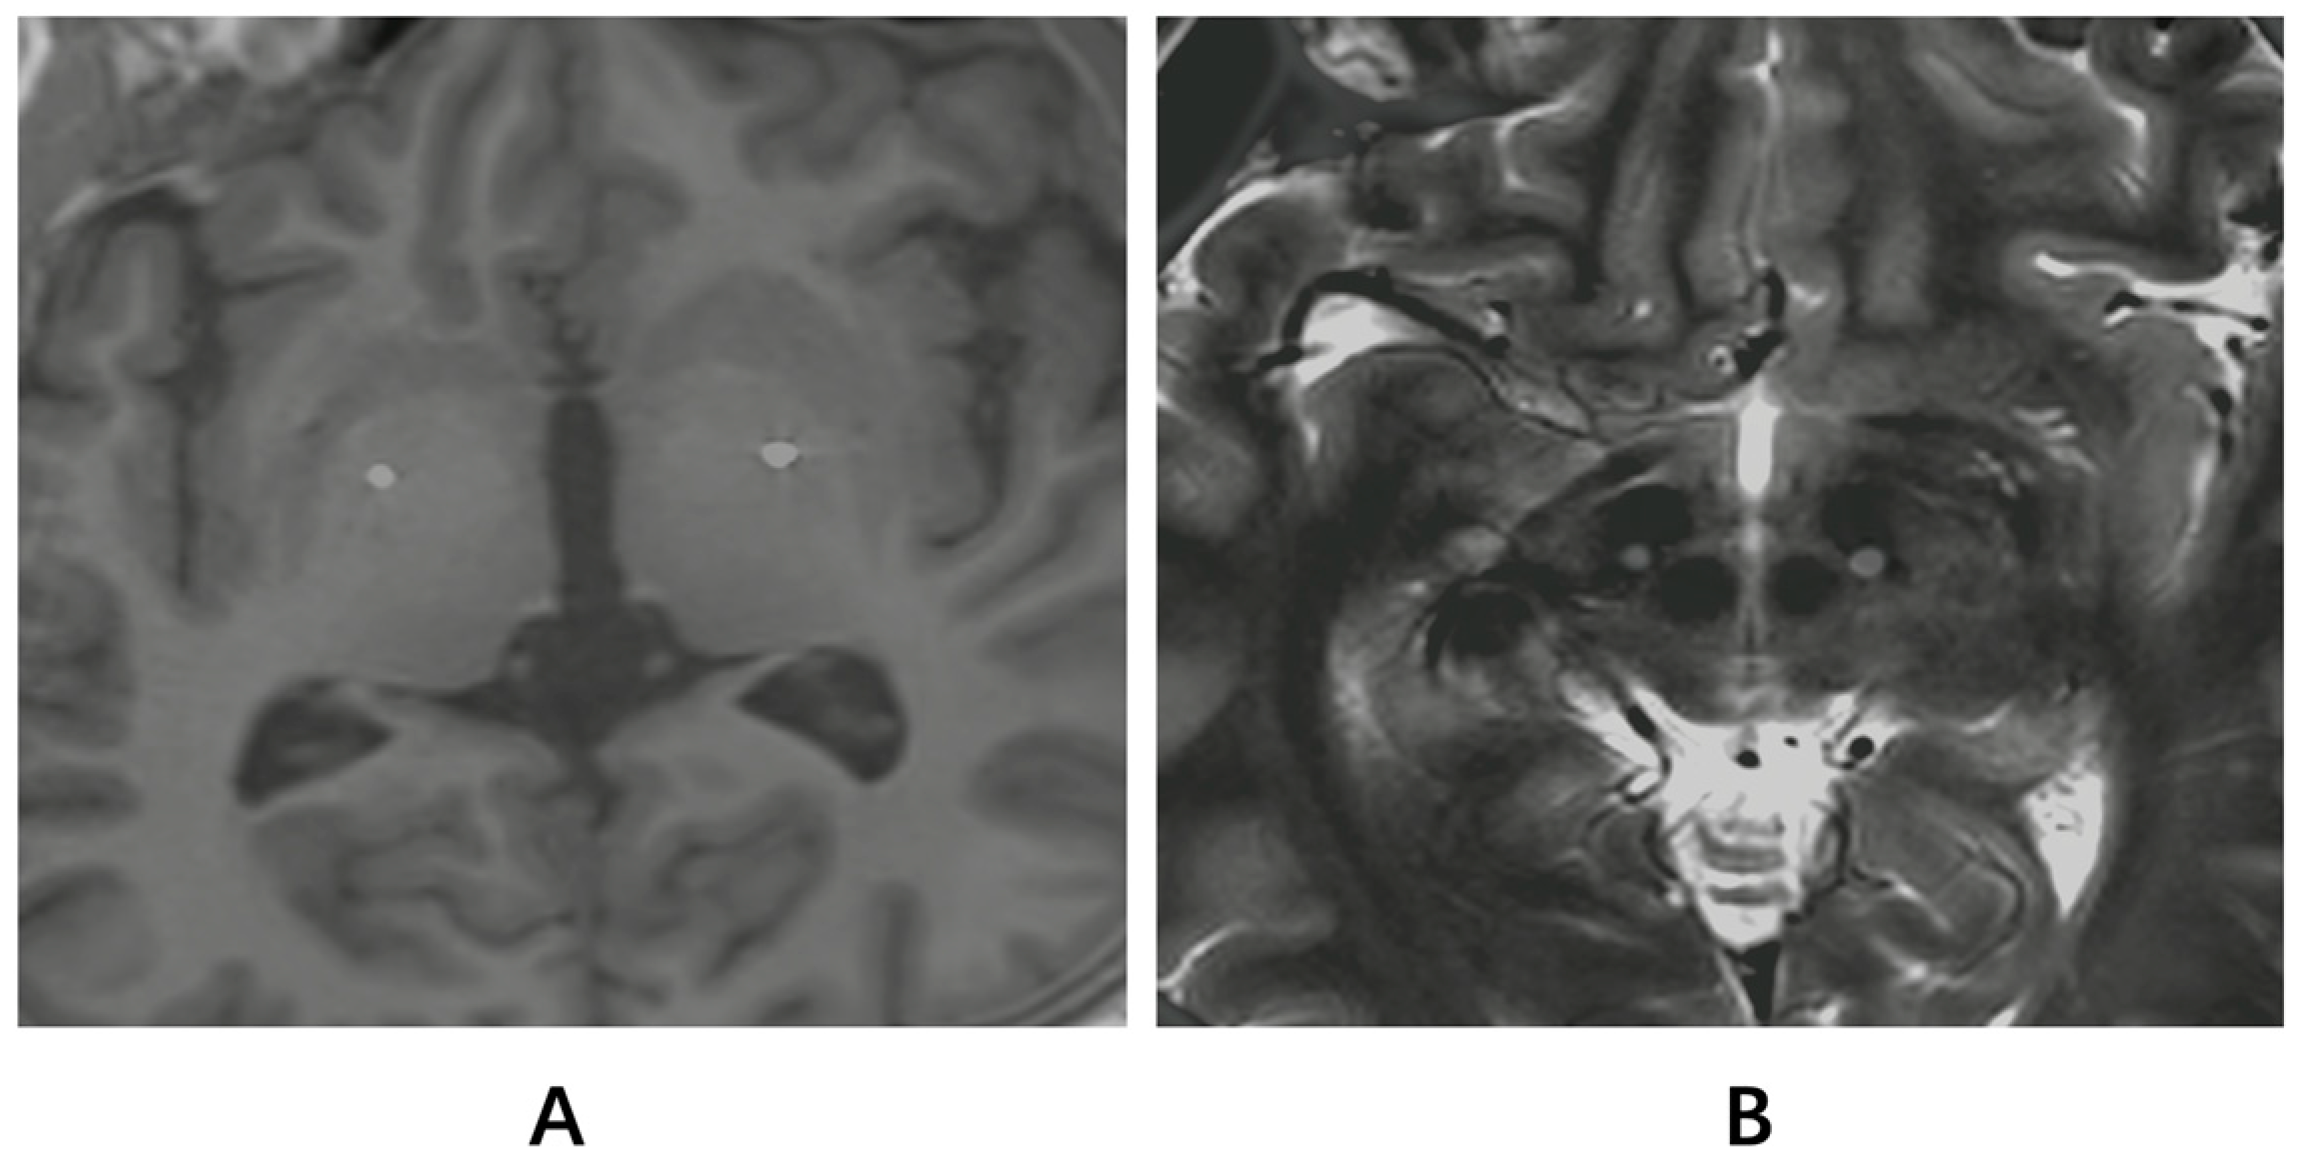

The clinical characteristics of the two groups of patients were similar at baseline in terms of age at surgery (26.12 ± 13.3 years in the GPi group vs. 19.67 ± 16.67 years in the STN group, p = 0.116); male sex (58.82% vs. 66.67%, respectively; p = 0.717); TOR1A mutation (17.65% vs. 8.33%, respectively; p = 0.622); age at onset (17.12 ± 16.75 years vs. 14.08 ± 17.89 years, respectively; p = 0.739) and symptom duration (107.18 ± 99.22 months vs. 65 ± 87.18 months, respectively; p = 0.422). The age at onset and symptom duration did not influence the outcomes. No significant differences were observed in motor function (BFMDRS-M or BFMDRS-D scores) or quality of life (SF-36) between the two groups at baseline (Table 2). The accuracy of electrode placement was confirmed by the fusion of the postoperative CT and preoperative MR images of one person using Matlab R2023a SPM 12 tool (Figure 1).

Figure 1.

Postoperative electrodeposition. (A) The figure shows the fusion of the postoperative CT and preoperative T1-weighted MR images of one person using the Matlab SPM tool. (B) The figure shows the fusion of the postoperative CT and preoperative T2-weighted MR images of one person using the Matlab SPM tool. (A): GPi. (B): STN.